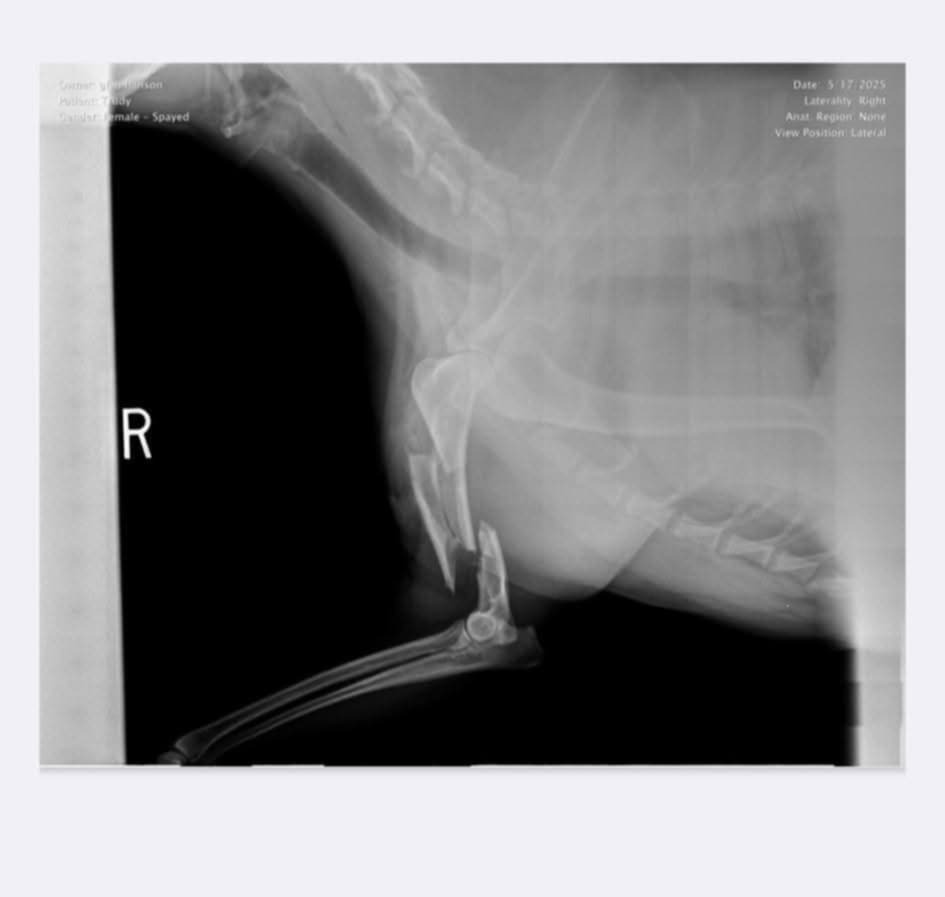

The neighbors and the neighbors dogs were out. We let our dogs out because we were working on the pool. Thank God we were outside otherwise Trudy wouldn't be here. Trudy was running the fence all excited, like dogs do. She runs fast and hard!! She got snagged up by the bolt holding the gate hinge, which caused her to crash, hard, into the gate post, which caused the many bone breaks. We thought the bolt cut an artery because she lost so much blood. Glen immediately put pressure on the cut while our neighbor called the vet, we use the same vet. Thank God she was out there too and had her wits because I lost mine.

Vet stopped the bleeding and stitched her up, put on a splint. We have to take her to a specialist for surgery. If surgery can't help, her leg will need to be amputated. Say prayers plz.